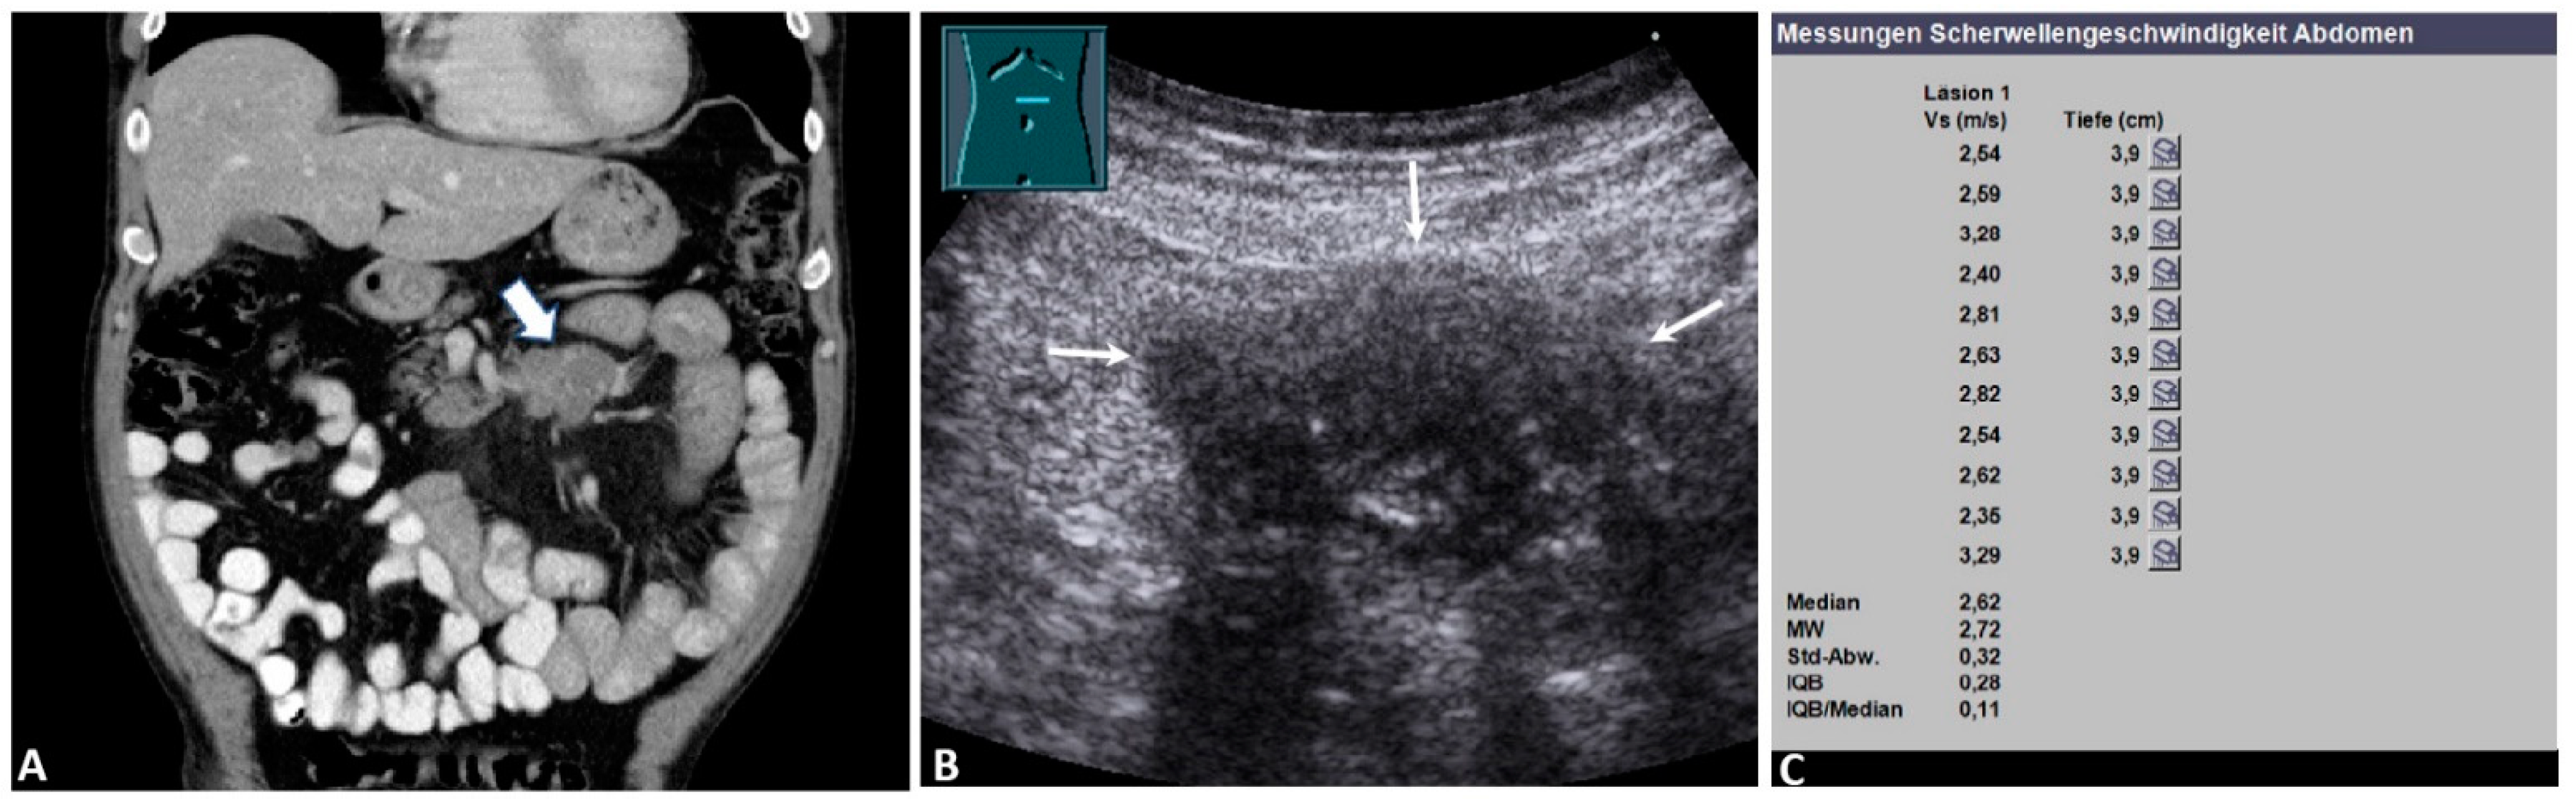

Figure 2.

Malignant mesenteric mass. A 67-year-old male patient with a known history of malignant lymphoma and suspected recurrence on staging. (A) Computed tomography showing a hypointense round mass in the left upper quadrant (arrow) (courtesy of Prof. Dr. Mahnken, Department of Radiology, University Hospital Marburg); (B) B-mode ultrasound showing a hypoechoic mesenteric mass (arrows); (C) the final acoustic radiation force impulse (ARFI) report of the same mass, showing a mean ARFI velocity (MW) of 2.72 m/s. The mesenteric histology showed a high-grade malignant lymphoma. Läsion 1: lesion 1; Vs (m/s): velocity in meter per second; Tiefe (cm): depth in centimeter; MW = mean value (Mittelwert); Std-Abw.: standard deviation (Standard Abweichung); IQB = interquartile range (Interquartilbereich).